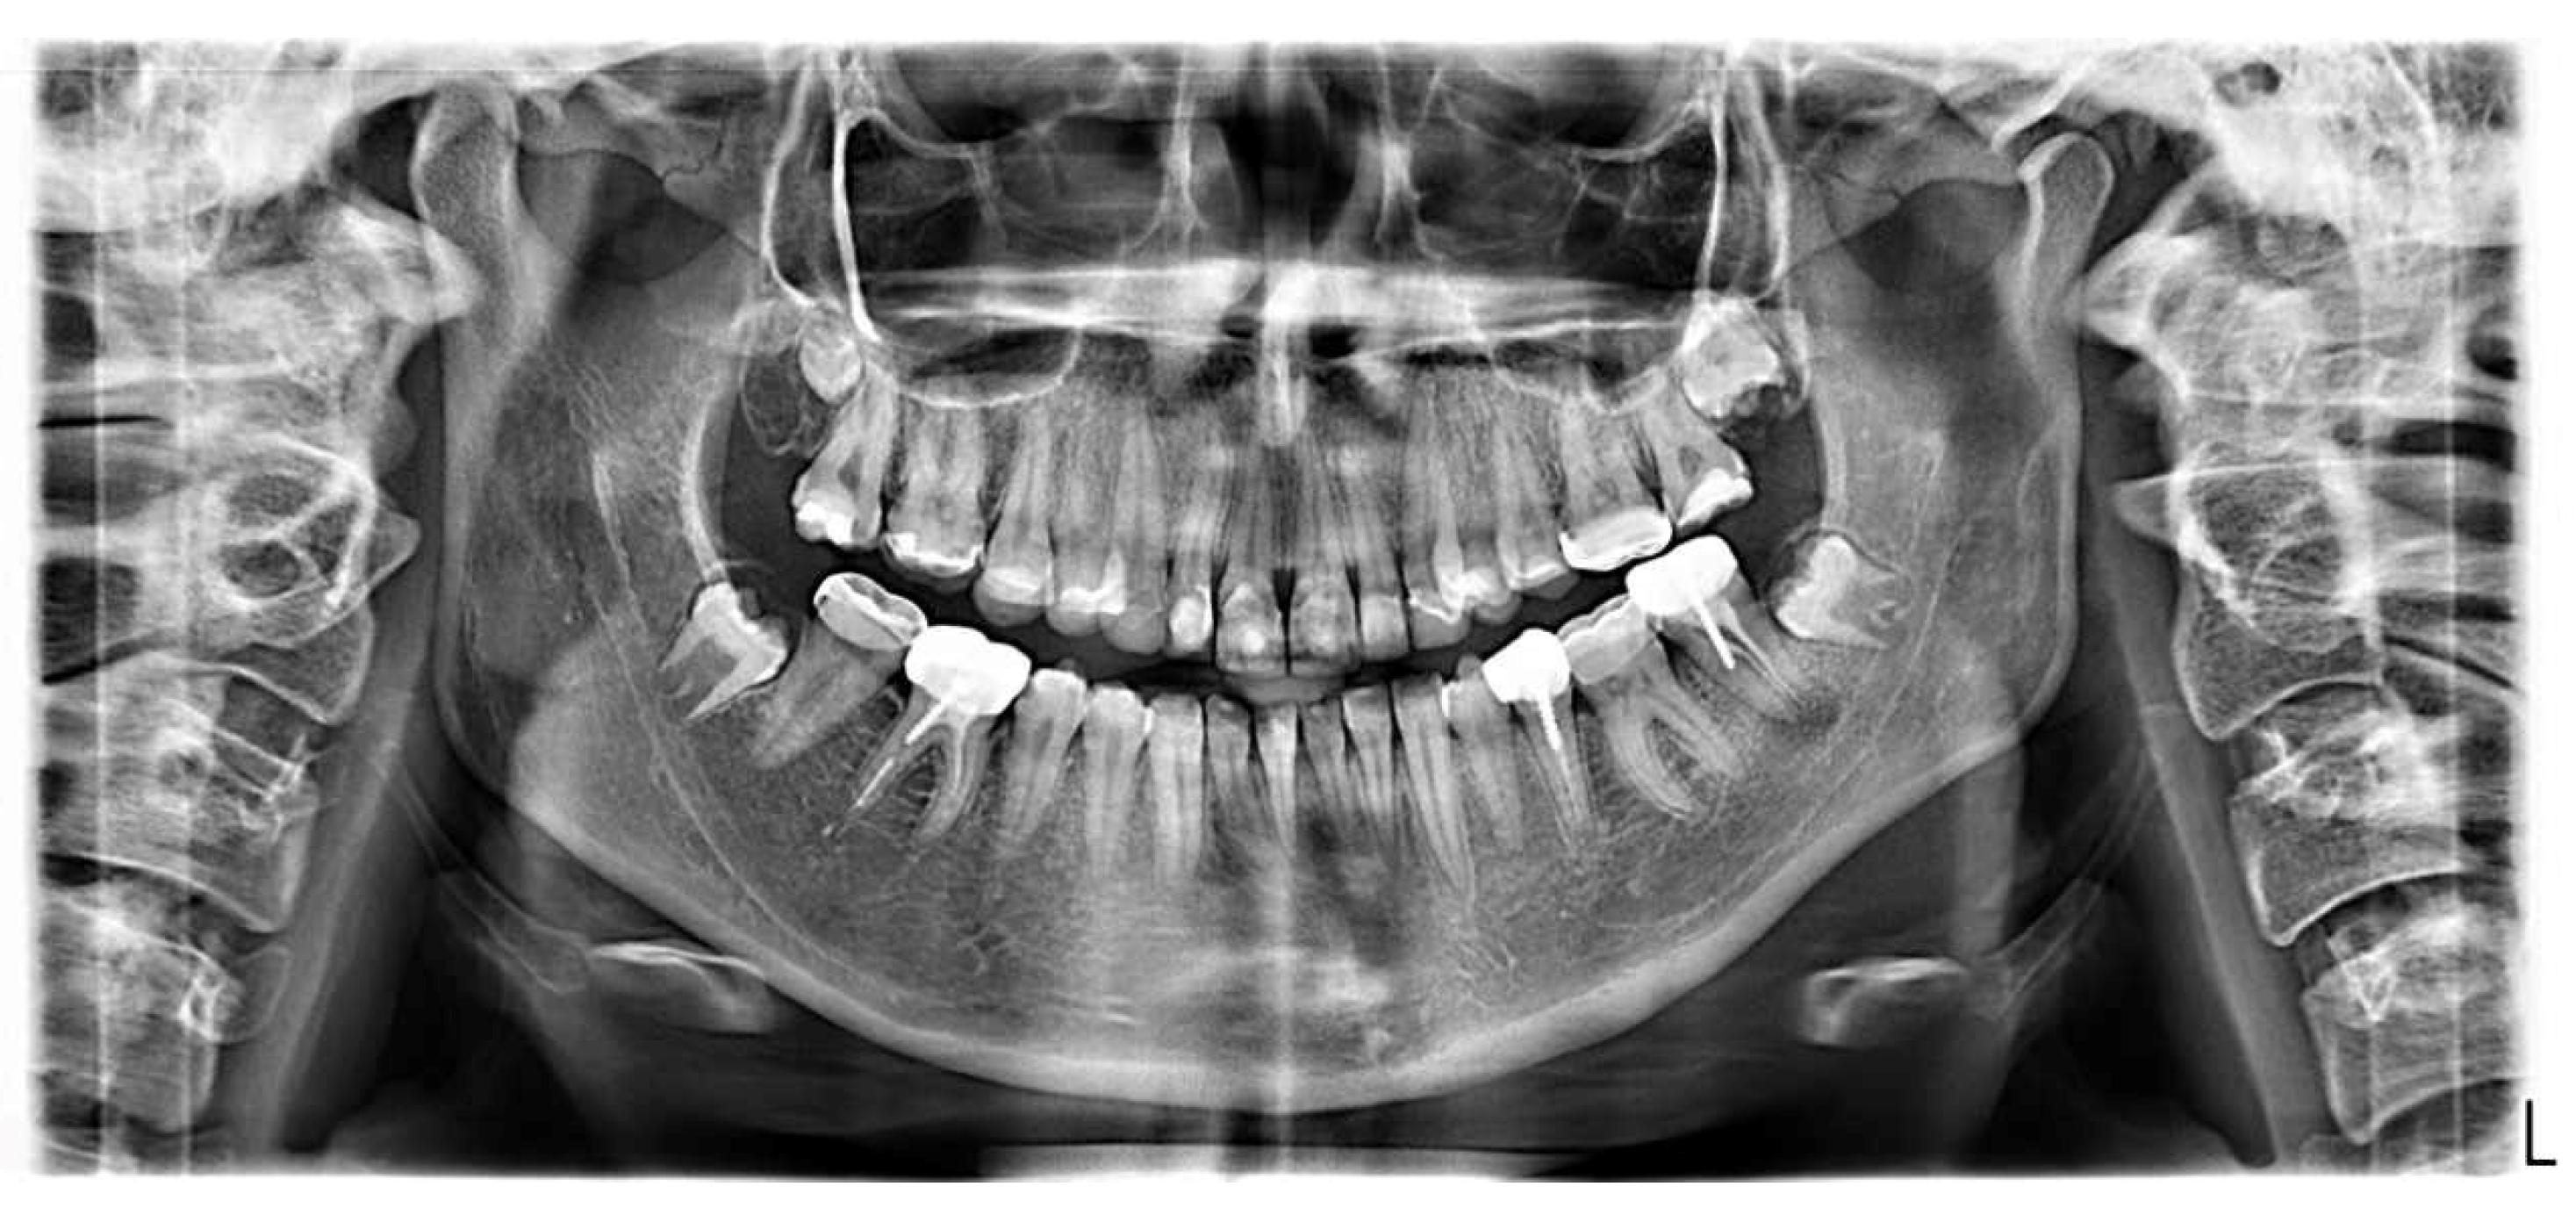

2.3. Radiographic Examinations